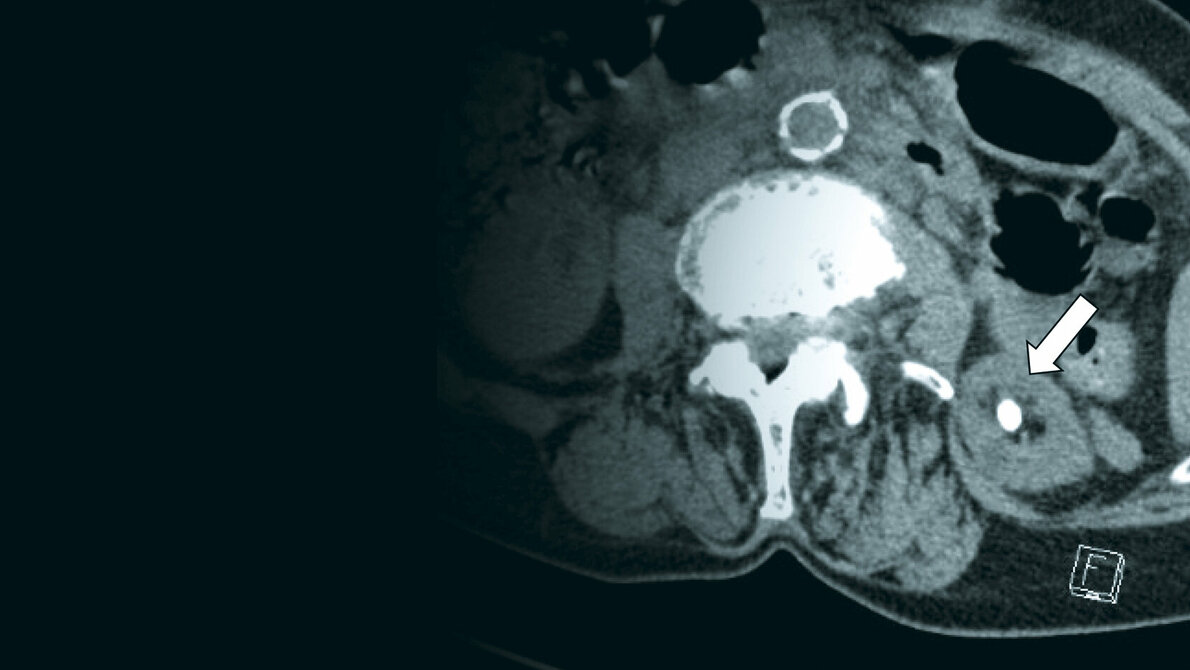

Zufallsbefunde: Nephrolithiasis

Die bildgebenden Verfahren spielen eine bedeutende Rolle in der Diagnostik, der Therapie und dem Follow-up von Patienten mit Nierensteinen. Mehrere Untersuchungsmethoden stehen zur Verfügung.

Die Nephrolithiasis ist eine komplexe Erkrankung. Verschiedene bildgebende Verfahren der Diagnostik und chirurgische Methoden in der Behandlung stehen zur Verfügung.